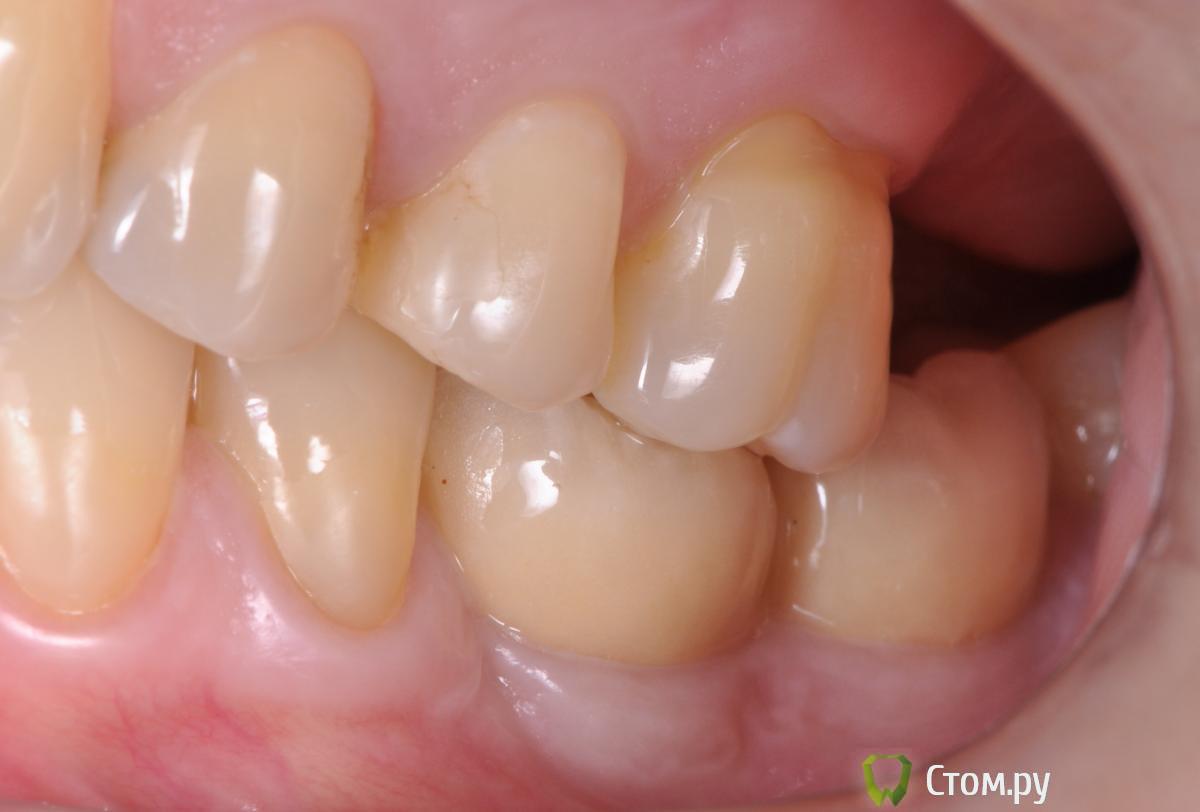

doctore Опубликовано 10 ноября, 2011 Поделиться Опубликовано 10 ноября, 2011 (изменено) ну эту картинку мы все видели ) хороший пример грамотных продаж ) Владислав, вы, как ментор Нобеля, наверняка сейчас активно начнете использовать новые имплантаты. Так вот, какая у вас будет форма абатмента на "нобель платформшифт" и "нобель ЦЦ" при установке Rp имплантата в дистальном отделе? Объем мягких тканей как раз таки легко создается десневой пластикой. Имплантолог,вероятно,крупно проигрался и задолжал.А тут две полные адентии откуда ни возьмись Согласен по поводу обьема и десневой пластики на 100%,но ведь в разумных пределах и при достаточной поддержке костной ткани(если она есть...Форма абатментов и результат,который я хочу видеть(это на Груви 4.3 и 5.0): Изменено 10 ноября, 2011 пользователем doctore Ссылка на комментарий

pit Опубликовано 11 ноября, 2011 Поделиться Опубликовано 11 ноября, 2011 (изменено) Имплантолог,вероятно,крупно проигрался и задолжал.А тут две полные адентии откуда ни возьмись Согласен по поводу обьема и десневой пластики на 100%,но ведь в разумных пределах и при достаточной поддержке костной ткани(если она есть...Форма абатментов и результат,который я хочу видеть(это на Груви 4.3 и 5.0): А Вы автор? И...... http://s42.radikal.ru/i096/1111/07/d9ba12a2a573.jpg Изменено 11 ноября, 2011 пользователем pit Ссылка на комментарий

doctore Опубликовано 11 ноября, 2011 Поделиться Опубликовано 11 ноября, 2011 (изменено) А Вы автор? И...... Пациентка одна-стороны разные.И хирургия и ортопедия мои. Изменено 11 ноября, 2011 пользователем doctore Ссылка на комментарий

pit Опубликовано 11 ноября, 2011 Поделиться Опубликовано 11 ноября, 2011 Пациентка одна-стороны разные.И хирургия и ортопедия мои.Очень даже симпатично. Исходные условия тоже хорошие. Десну формировали апикальным смещением и временными коронками?Нагрузили имплантаты одномоментно ли вторым этапом? В свете Ваших приципов идеализации лечения, этот кейс выглядит не завершенным, позвольте пульнуть камушек в Ваш огород))))))))))))))))))))))) Почему Вы не сделали интрузию 26 зуба и не установили имплант в позицию 27 зуба? ( спрашиваю как ортопед) А вобщем работа понравилась и врачебное, и техническое исполнение Ссылка на комментарий

Большой Зеленый Опубликовано 11 ноября, 2011 Поделиться Опубликовано 11 ноября, 2011 Красиво Ссылка на комментарий

Bobby Опубликовано 11 ноября, 2011 Автор Поделиться Опубликовано 11 ноября, 2011 Пациентка одна-стороны разные.И хирургия и ортопедия мои. Владислав, подскажите, а зачем соединяли 3.6 и 3.7 ? Ссылка на комментарий